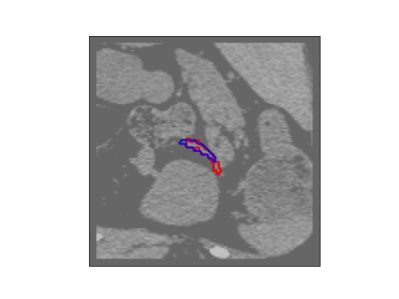

The human annotations are imperfect, especially when produced by junior practitioners. Multi-expert consensus is usually regarded as golden standard, while this annotation protocol is too expensive to implement in many real-world projects. In this study, we propose a method to refine human annotation, named Neural Annotation Refinement (NeAR). It is based on a learnable implicit function, which decodes a latent vector into represented shape. By integrating the appearance as an input of implicit functions, the appearance-aware NeAR fixes the annotation artefacts. Our method is demonstrated on the application of adrenal gland analysis. We first show that the NeAR can repair distorted golden standards on a public adrenal gland segmentation dataset. Besides, we develop a new Adrenal gLand ANalysis (ALAN) dataset with the proposed NeAR, where each case consists of a 3D shape of adrenal gland and its diagnosis label (normal vs. abnormal) assigned by experts. We show that models trained on the shapes repaired by the NeAR can diagnose adrenal glands better than the original ones. The ALAN dataset will be open-source, with 1,594 shapes for adrenal gland diagnosis, which serves as a new benchmark for medical shape analysis. Code and dataset are available at https://github.com/M3DV/NeAR.